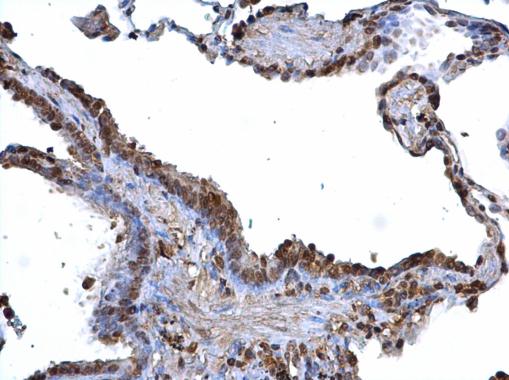

ARID3B antibody detects ARID3B protein at nucleus on human lung carcinoma by immunohistochemical analysis.

Sample: Paraffin-embedded human lung carcinoma.

ARID3B antibody (GTX129352) dilution: 1:100.

Antigen Retrieval: Trilogy™ (EDTA based, pH 8.0) buffer, 15min